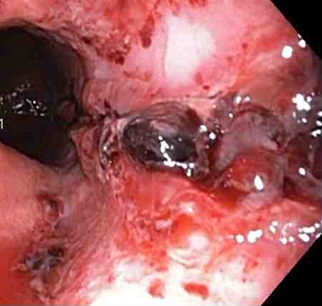

Mallory Weiss tear following cauterisation with a bipolar probeFrom the personal collection of Douglas Adler; used with permission

Thermal coagulation

This includes multipolar electrocoagulation or heater probe.

Thermal coagulation is safe and often successful when given by experienced operators.[79][80]